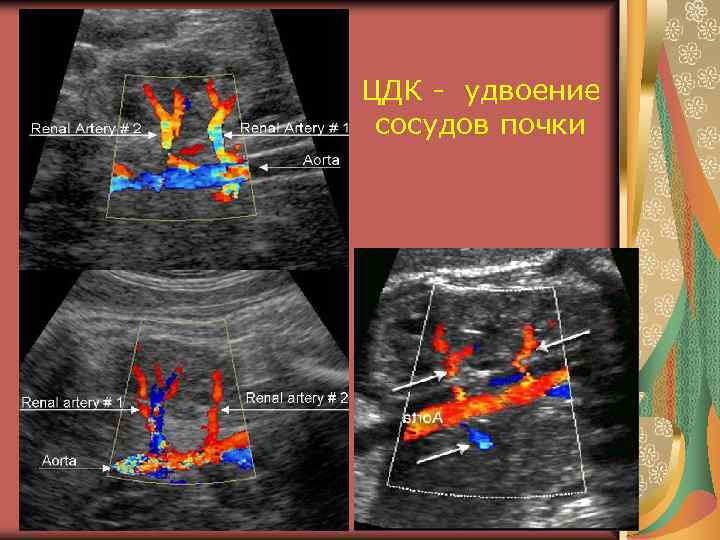

УЗ признаки удвоенной почки 1. Паренхиматозная или фиброзная перегородка, разделяющая почечный синус 1. Увеличение вертикального размера по сравнению с контрлатеральной почкой или средними возрастными размерами более, чем на 2 см 2. Нарушение соотношения между размерами (в норма 1 х2 х3) 3. Уменьшение угла между длинной осью и средней линией (менее 20º) 4. Ограничение подвижности 5. 2 магистральные почечные артерии и вены, 2 мочеточника (2 ворот)

Удвоенная почка 1. 2 ворот 2. 2 почечные артерии 3. Фиброзная перегородка

ЦДК - удвоение сосудов почки